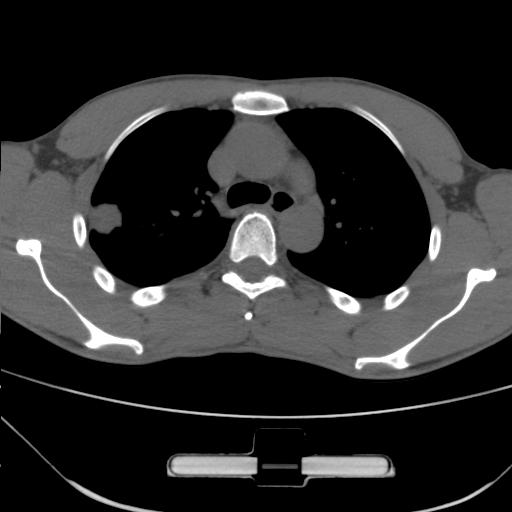

右肺上叶后段近胸膜下结节样异常密度灶,似见分页及毛刺,考虑右肺上叶周围型肺ca,建议穿刺病理检查

缺乏病史,症状体征,但这个孤立结节具备了几乎所有的恶性征象:分叶,毛刺,空泡征,胸膜凹陷征,血管集束。